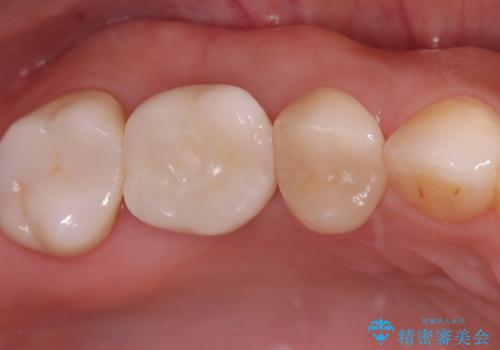

- 右上の6番の奥歯の痛みを主訴に来院されました。精密検査の結果、根管内を歯科用顕微鏡で確認したところ、肉眼では見えないクラック(ひび割れ)が発見されました。このクラックが痛みの原因であり、将来的に歯の保存が難しいと判断。患者様と話し合い、歯を残すことを諦め、抜歯と同時にインプラントを埋入する抜歯即時埋入インプラントによる治療計画を立案しました。これにより、治療期間と身体への負担を最小限に抑え、確実な解決を目指しました。

今回の治療では、まず原因となっていた奥歯を慎重に抜歯し、その直後にインプラントを埋入しました。この抜歯即時埋入により、抜歯からインプラント埋入までの期間を省き、骨の吸収を最小限に抑えられました。治療後は痛みや腫れも少なく、患者様は快適に過ごしていただけました。最終的に、わずか3ヶ月でセラミッククラウンを装着。機能性と審美性を兼ね備えた新しい歯により、長年の痛みが解消され、快適な食生活を取り戻していただけました。